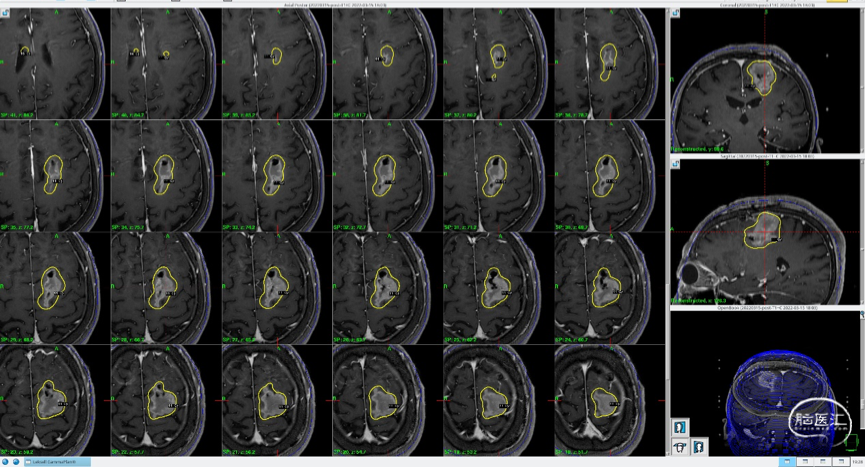

磁共振MRI定位扫描(T1增强序列,1mm轴位连续断层薄扫)。

磁共振MRI定位扫描(T2平扫,2mm轴位连续断层+T1增强序列,1mm轴位连续断层薄扫)。

制定立体定向伽玛刀治疗计划(术中薄扫核磁扫面共发现4个病灶,除术前的2个病灶外,还发现2个小病灶);

1)左额囊性病灶治疗计划(分期治疗):边缘剂量11Gy(55%,中心20Gy),照射体积:16.563cm3。

将患者摆位至伽玛刀机器上,进行照射。

总照射时长:75.6分钟